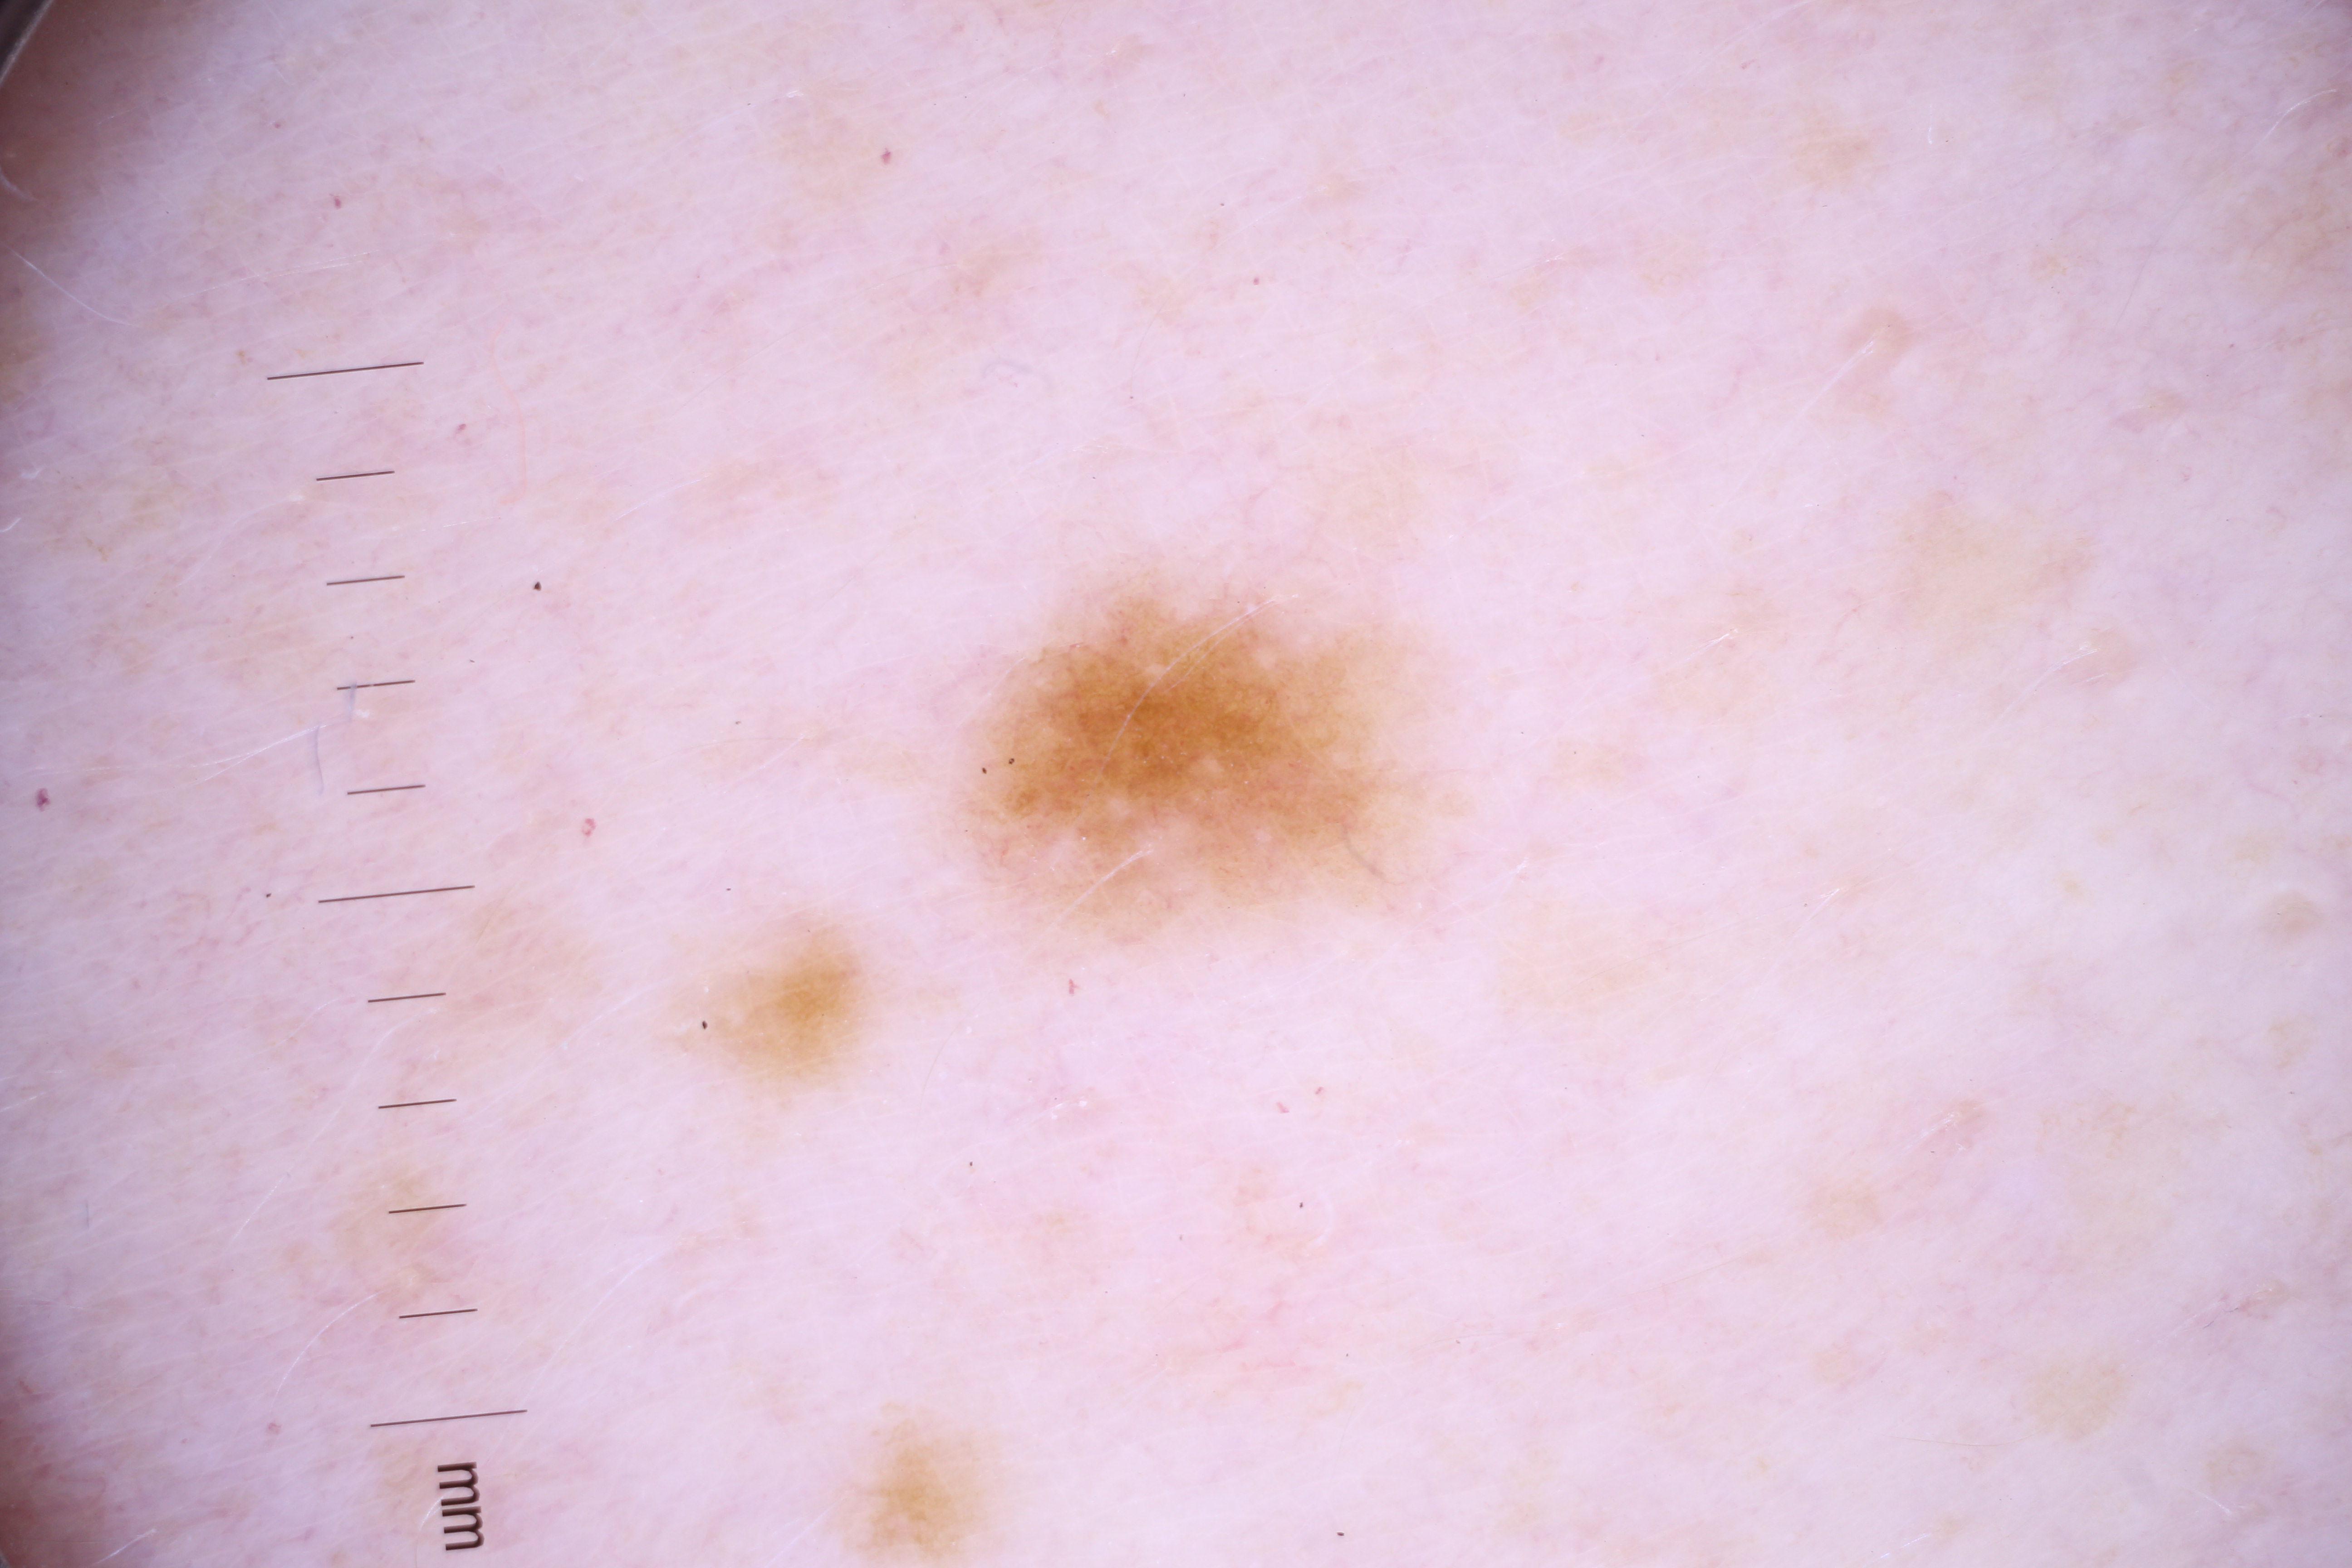

ISIC_4077341

Information

- Created

- Dimensions

- 5184 x 3456

- Attribute to

- The University of Queensland Diamantina Institute, The University of Queensland, Dermatology Research Centre

- License

- CC-BY

- Used in

- Challenge 2020: Training

- Belongs to

- IP_1969685 IL_9238622

Clinical

| Field | Value |

|---|---|

| acquisition_day | 1 |

| age_approx | 50 |

| anatom_site_1 | Trunk |

| anatom_site_2 | Anterior trunk |

| concomitant_biopsy | False |

| dermoscopic_type | contact non-polarized |

| diagnosis_1 | Benign |

| diagnosis_confirm_type | serial imaging showing no change |

| family_hx_mm | False |

| image_type | dermoscopic |

| lesion_id | IL_9238622 |

| patient_id | IP_1969685 |

| personal_hx_mm | True |

| sex | male |